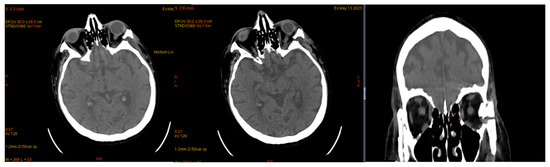

| January 2023 | second extramedullary relapse bilateral ocular left eye clinically, imaging, and biopsy demonstrated right eye demonstrated by imaging | methotrexate, asparaginase, calcium folinate radiotherapy, 30 gy/15 sessions result: imaging complete remission |